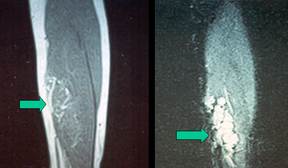

Intramuscular hemangioma is a rare condition; it differs from infantile hemangioma simply because it occurs in patients older than children (Image 9.4).

Image 9.4 T1 and T2 MRI images of intramuscular hemangioma of the leg.

This condition is commonly confused with other hemangiomas. Most cases described as "intramuscular hemangioma" in the literature actually represent soft tissue venous malformations. This confusion cause inappropriate referrals, imaging studies and even therapeutic interventions in significant number of patients. Therefore, it is important to distinguish these two conditions (intramuscular hemangioma versus soft tissue venous malformation).

Intramuscular hemangioma can be seen in any age, commonly diagnosed in early adulthood. In contrast to venous malformations, intramuscular hemangiomas have arterial feeders and in contrast to AVMs, these vascular birthmarks do not demonstrate arteriovenous shunting.

Overall, these lesions are benign anomalies. However, most lesions are problematic causing pain and discomfort and demonstrate progressive enlargement in some patients. Because of the fact that they are located in the muscle tissue, most patients experience various degrees of pain.